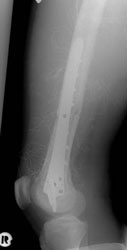

Abb. 8a: Die zweidimensionale Planung erlaubt keine Implantation in der regio 35 und 36 aufgrund des Verlaufes des N.alveolaris inferior.

Abb. 8b: Die dreidimensionale Planung und die anschließende Nutzung der Führungsschablone macht die Implantation regio 35 und 36 möglich.